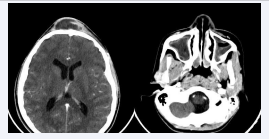

A contrast-enhanced CT scan was performed, and revealed the presence of an enhanced collection in the anterior frontal soft tissues, with a large defect in both anterior and posterior walls of the frontal sinus; complicating an active sinusitis but no abnormalities in the brain parenchyma [Figure 3,4].

Pan-sinusitis with frontal abscess.

Figure 3: Pan-sinusitis with frontal abscess.

CT scan in sagittal section: Defect of anterior and posterior walls of the frontal sinus with abscess.

Figure 4: CT scan in sagittal section: Defect of anterior and posterior walls of the frontal sinus with abscess.

Diagnosis is confirmed by contrast-enhanced CT scan, while MRI allows for better characterization of the intracranial extension [7]. In our case, an urgent craniofacial contrastenhanced CT scan was performed, revealing the presence of a collection in the anterior medial frontal soft tissues that enhanced peripherally after contrast injection. Additionally, a defect in the anterior and posterior walls of the frontal sinus was identified, complicating an active acute pan sinusitis without clear delineation of a cerebral complication.